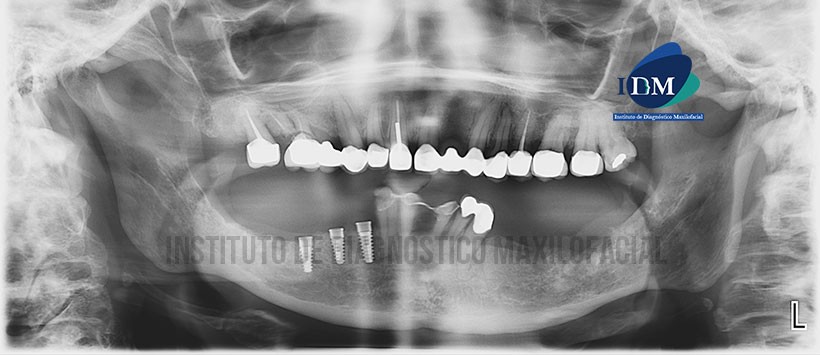

En la radiografía panorámica (Figura 1) se observa una alteración en la morfología del hueso alveolar en zona mandibular izquierda asociado a un aumento de volumen del tejido blando adyacente.